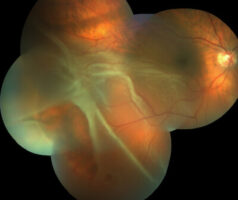

Retinal Detachment: What is it?

This photo montage shows a retinal detachment. The white areas of the retina are the detached portion, as it is elevated above the back surface of the eye. If left untreated, this may cause permanent impaired vision. Some early signs of retinal detachment are flashes of light and a sudden onset of floaters. If you… Read More